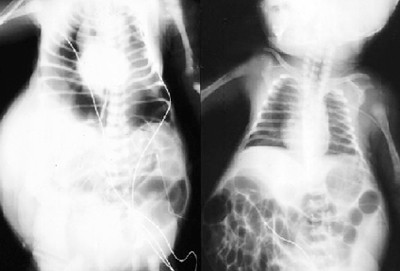

Sau khi sinh, siêu âm và chụp Xquang có thể xác định được các tổn thương bất thường về đường tiết niệu. Ảnh: Tổn thương mất cơ bụng trên phim Xquang.